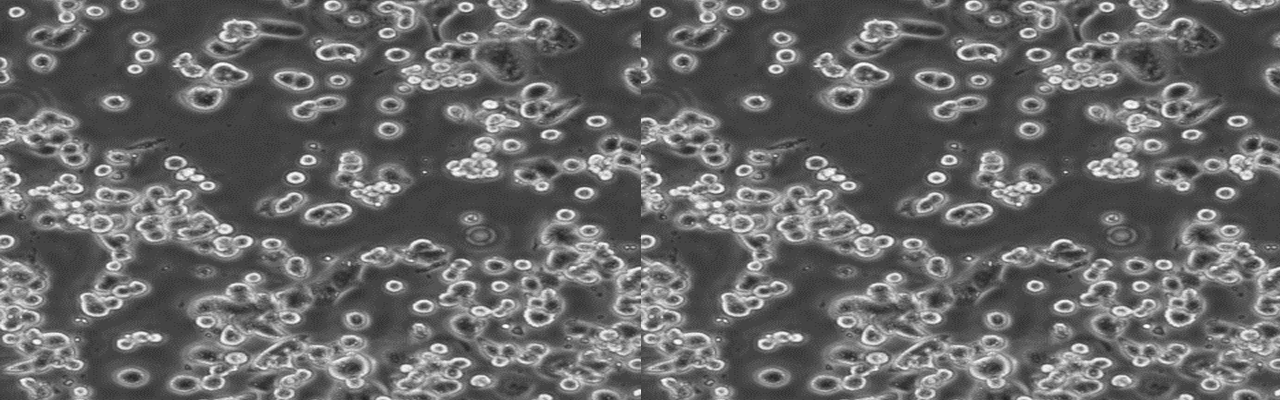

| 细胞全名 | 小鼠脑神经胶质母细胞瘤瘤株;G422 |

| 生长特性: | 贴壁生长 |

背景资料:1964年建株;甲基胆蒽植入Km小鼠脑内诱发星形细胞瘤,传至第120代后转为胶质细胞瘤;瘤细胞悬液同系小鼠皮下、肌肉、脑内移植,成功率皆100%。肌肉及脑内移植可形成较规律的移植性瘤株,存活时间脑内型15.9±4.8天;肌肉型20.3±6.6天。